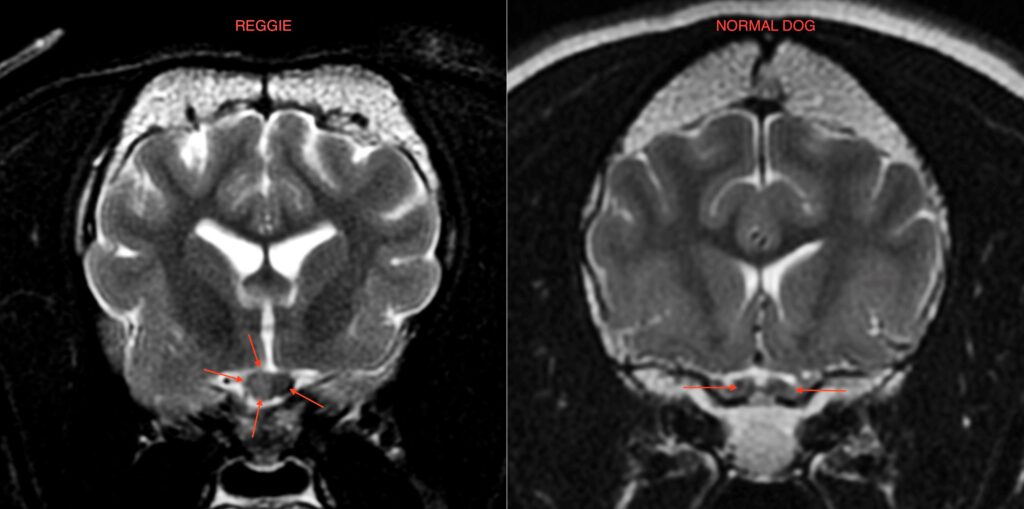

Seven-month-old Reggie came to visit our Ophthalmology Team with a history of sudden onset bilateral blindness. He was understandably anxious and quiet when he first arrived. After a full ophthalmic examination, Bilateral Optic Neuritis (a condition where the optic nerve becomes inflamed) was suspected. Magnetic resonance imaging (MRI) of the brain confirmed the diagnosis. Infectious diseases were ruled out and a CSF (cerebrospinal fluid) sample confirmed an inflammatory process.